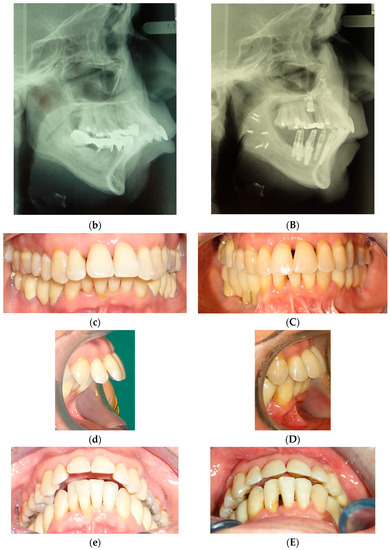

Figure 6.

A 40-year female patient with II dento-skeletal malocclusion: orthopanoramic, VTO, and intraoral views before (a–e) and after orthodontic surgery and new prosthetic rehabilitation (A–E).